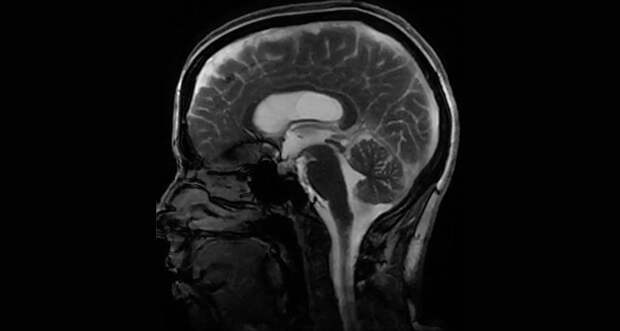

With every heartbeat, fluid squishes through the brain and jiggles it like a bowl full of jelly.

A new twist on magnetic resonance imaging illuminates these pulsing brain ripples, movements so subtle that they had escaped detection by current imaging technology. Abnormal brain motion could signal trouble, such as aneurysms or damage from a concussion.

In the new work, scientists honed an existing method called amplified MRI, a technique that stitches together multiple images taken at precise times of the heartbeat. Using an algorithm…